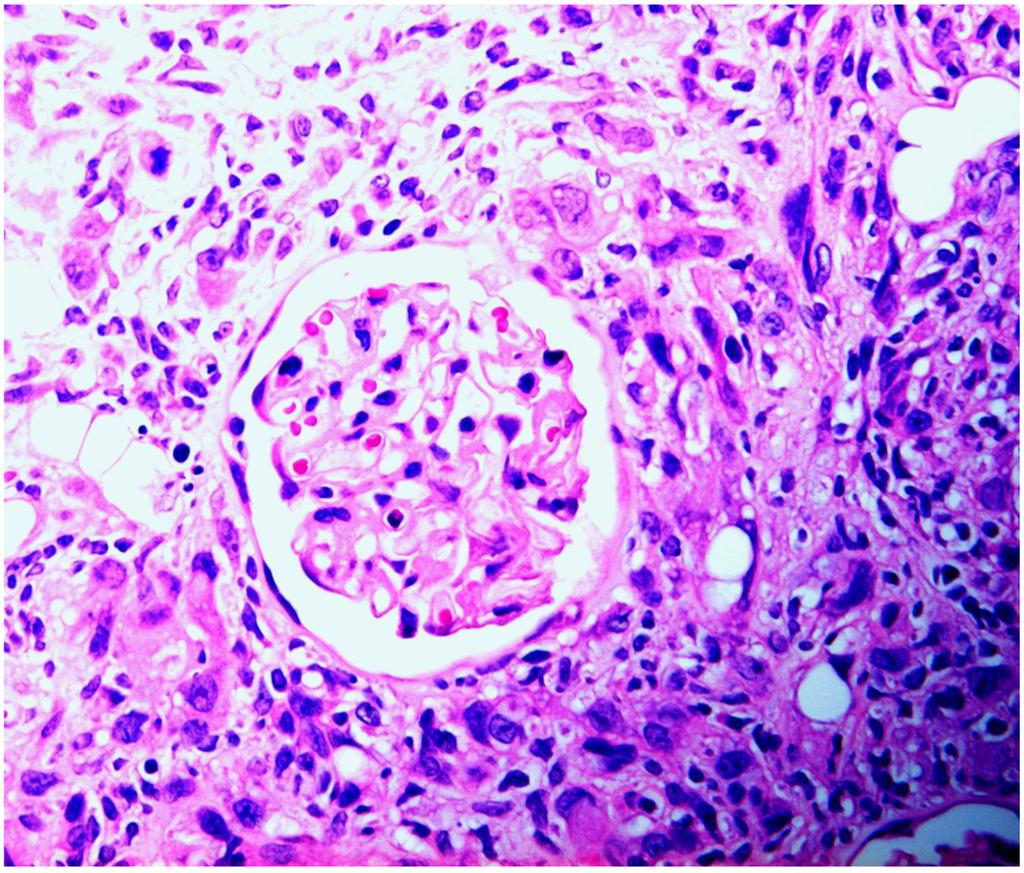

Figure 4.

Rat renal carcinoma, characterized by disorganized proliferation of cells with pleomorphic nuclei, infiltrating (left) into cortex and enveloping an intact glomerulus.

The present situation with respect to nephrotoxicity of P. polonicum has echoes of a mycotoxicosis caused by Fusarium verticilliodes, described in its first report [29] as hepatocarcinoma and oesophageal basal cell hyperplasia in rats fed an artificially moulded dietary component. The finding generated wide interest, particularly in the USA, because the fungus readily causes spoilage of maize. There was also a regional hypothesis concerning putative involvement in hotspots of human oesophageal cancer in the Republic of Transkei. Subsequent studies in South Africa recognised the new mycotoxin fumonisin B1 as causing diverse toxicological responses in horse (leukoencephalomalacia), pig (pulmonary oedema) and rat (renal carcinoma). For the latter, a comprehensive 2-year toxicology study has been made [30], revealing male-specific renal carcinoma. Concurrently, Hard et al. [31] stated “carcinomas induced by fumonisin B1 were predominantly a rare and highly malignant variant of renal tubule tumour capable of infiltrative growth invading between tubules and glomeruli, sequestering these pre-existent elements as entrapped remnants within the tumour mass.” Much the same could be said concerning male rat renal tumours in response to ochratoxin A, with respect to envelopment of glomeruli (Figure 4). Hard et al. [31] also recognised sarcomatoid areas in the National Toxicology Program’s fumonisin renal tumours; a similar sarcomatoid component of mammary tumour has also recently been recognised in a female rat given the tumour promoter sodium barbitate in drinking water after chronic dietary exposure to ochratoxin A [32].